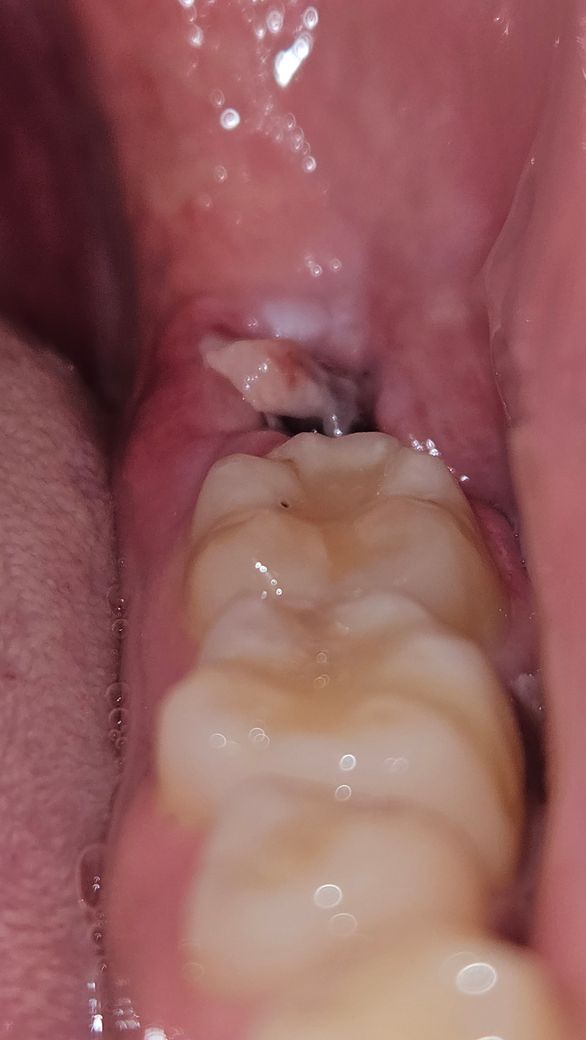

사랑니 양쪽 발치 6일차인데 저거 조심히 떼어내거나 떨어져나가도 괜찮나요?

반대쪽은 인터넷에서 본 회복 사진처럼 점점 채워지는게 보이는데 이 쪽은 저 하얀 덩어리 같은게 상처부위를 가리고 있습니다. 저거 정체가 뭔가요?

현재 발치부위가 아물면서 혈병이 생긴 것으로 보이며, 억지로 떼어내거나 하지말고 그냥두길 권합니다.

잇몸에 상처가 치유되면서 생기는 자연스러운 현상이니 일부러 제거를 하실필요는 없습니다.

하얀색 막은 상피세포로 그대로 두시면 됩니다. 잇몸이 닫히는 과정에서 자연스럽게 생깁니다.